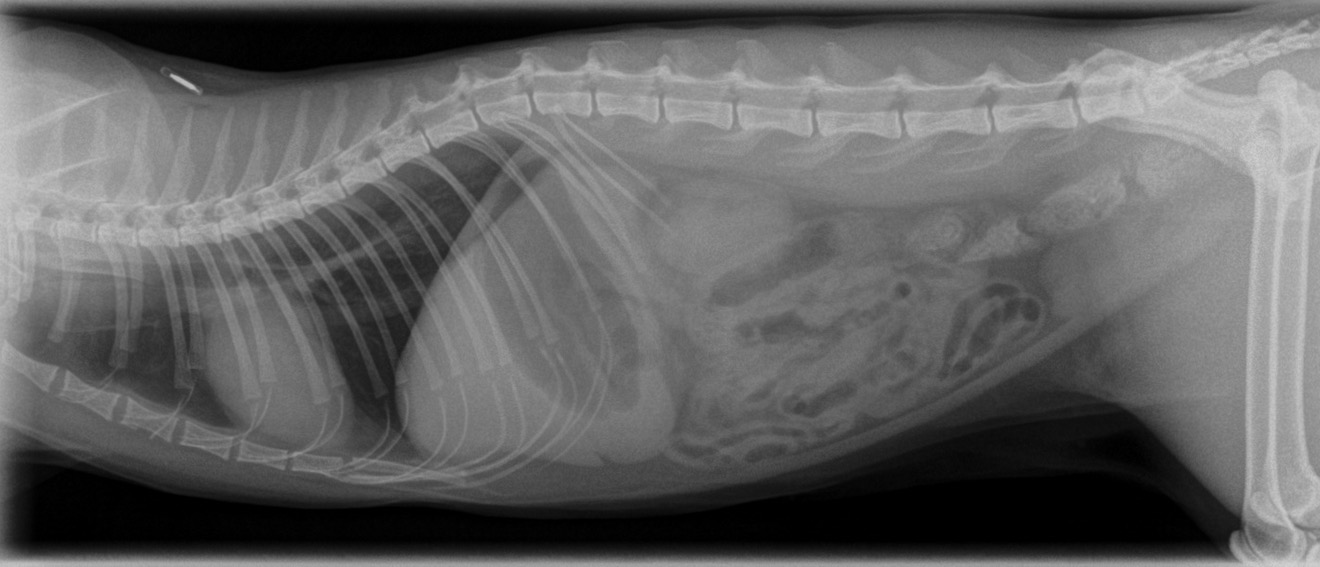

When Cat & Car Collide Feline Road Trauma Walkerville Vet Can A Cat Dislocate Its Back Leg Work your way up the limb, identifying areas of tenderness by. Fractures and dislocations of the spinal cord can result. if you’ve ever broken a leg yourself, or know a friend, family member or colleague who has, you may well be. Traumatic injuries can cause changes to a cat’s back legs in different ways. most cats will pull. Can A Cat Dislocate Its Back Leg.